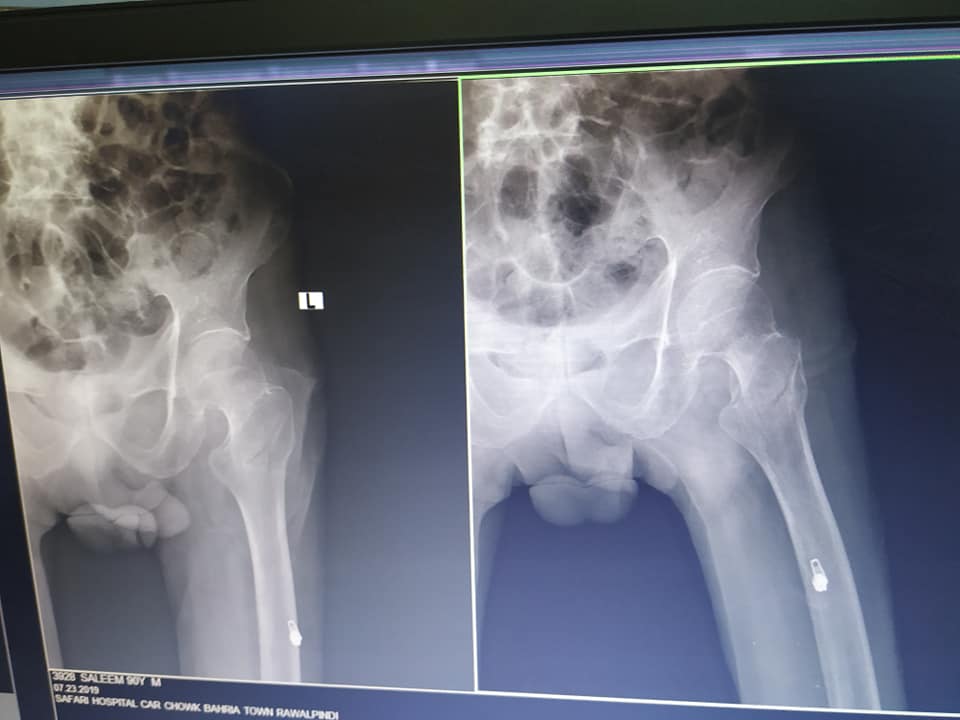

Asking for Other, Male, 90 years old, Islamabad

my grand father slipped on floor yesterday. kindly have a look on x ray i need dr opinion is this fracture is curable without surgery as his age 90 and suffering from weakness blood pressure low and no eating well please dr suggest best possible treatment

This patient needs surgery provided he would be cleared from anaesthesia department for surgery

Hi, he needs operation for this fracture to be able to walk again. Thanks

this fracture happens most commonly in old age and best solution is to perform surgery as soon possible.

if you don't get surgery, old people will suffer in bed due to complications

The best approach is to operate and mobilise him as soon as possible, because for him to be in bed is to invite very high risk.

this fracture needs to stabilize as early as possible